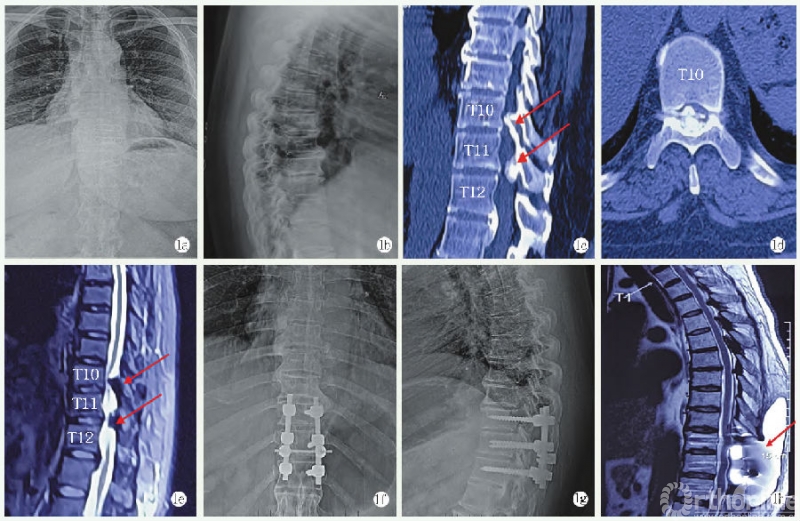

图1 患者女,48岁,胸椎黄韧带骨化症(T10/11、11/12)1a,1b:术前胸椎正侧位X线片;1c:矢状位CT示T10/11、T11/12黄韧带骨化;1d:轴位CT示T10/11严重椎管狭窄,Sato分型为结节型;1e:MRI示T10/11、T11/12黄韧带骨化,髓内高信号影;1f,1g:术后X线片见内固定位置良好;1h:术后MRI示CSFL并皮下积液

纳入标准:(1)诊断为胸椎黄韧带骨化症[3];(2)手术方式为后路全椎板切除术;(3)具有完整的病例资料及影像学数据(图1a~1e)。

神经剥离子小心分离黄韧带与硬膜粘连部分,切除骨化黄韧带,探查上下节段椎管内空间,见无明显压迫,脊髓完全减压。打磨双侧关节突关节,适当植骨,后给予连接棒适当角度,安装内固定系统(图1f,1g)。

CSFL诊断标准:(1)手术中硬膜破裂或有透明液体流出;(2)术后引流管持续排出大量淡红色血性液体,出现头疼、头晕、恶心等低颅压症状;(3)通过皮下穿刺或抽吸透明液体证实,或有影像资料确认(图1h)。